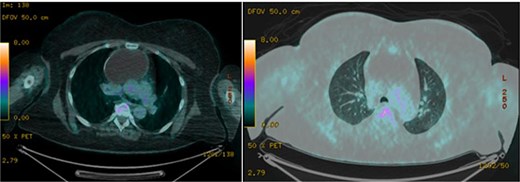

A 51-year-old woman with a history of insulin-dependent type 2 diabetes mellitus and Henoch-Schönlein purpura without history of tobacco or alcohol use presented to the emergency department after being struck by a slow-moving motor vehicle as a pedestrian. On initial evaluation, the patient reported mild shoulder pain but denied any further injuries or symptoms. Workup included a chest X-ray, which demonstrated mediastinal widening suggestive of thoracic aortic ectasia. Non-contrast computed tomography (CT) of the chest revealed a large fluid density in the anterior mediastinum with rim calcification, subtle septations, and some nodularity, measuring 7.1 × 9.2 × 11.2 cm, accompanied by multiple small bilateral pulmonary nodules (Fig. 1). The radiologist was concerned about a possible cystic teratoma. A subsequent positron emission tomography (PET-CT) scan confirmed a photopenic mass in the anterior mediastinum measuring 7.0 × 9.4 cm, with no evidence of regional lymphadenopathy (Fig. 2). The patient remained asymptomatic and elected to undergo surgical resection.

Coronal and axial views of a non-contrast CT of the chest demonstrating a large fluid density in the anterior mediastinum with rim calcification, subtle septations, and some nodularity, measuring 7.1 × 9.2 × 11.2 cm, accompanied by multiple small bilateral pulmonary nodules.